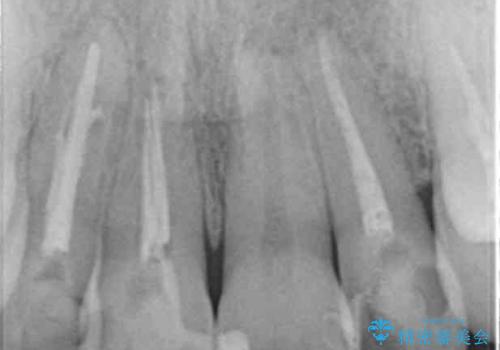

CT撮影を行った結果、右上前歯は吸収が進み抜歯が必要な状態です、

抜歯をせず放置すると、より吸収が進み臨在する歯にも悪影響を及ぼしてしまう可能性が考えられます。

上顎4前歯は、根管治療の既往があり、虫歯も見られたことからブリッジによる治療で審美性の回復を行うとともに臨在歯の虫歯もセラミック治療を行っていきます。